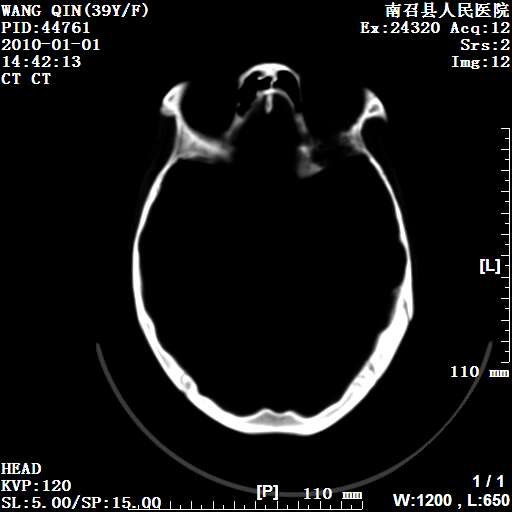

以下是引用随光逐影在2010-1-22 9:03:00的发言:[br]考虑左侧中颅窝(蝶骨翼区)脑膜瘤侵犯蝶骨翼并突入左侧眼眶。

以下是引用水过无痕在2010-1-22 14:55:00的发言:[br]一、定位:颅外占位;二、定性:恶性可能性大;三、组织来源:来源于左侧眼外直肌或其他部位;考虑为:横纹肌肉瘤>转移瘤>脑膜瘤.